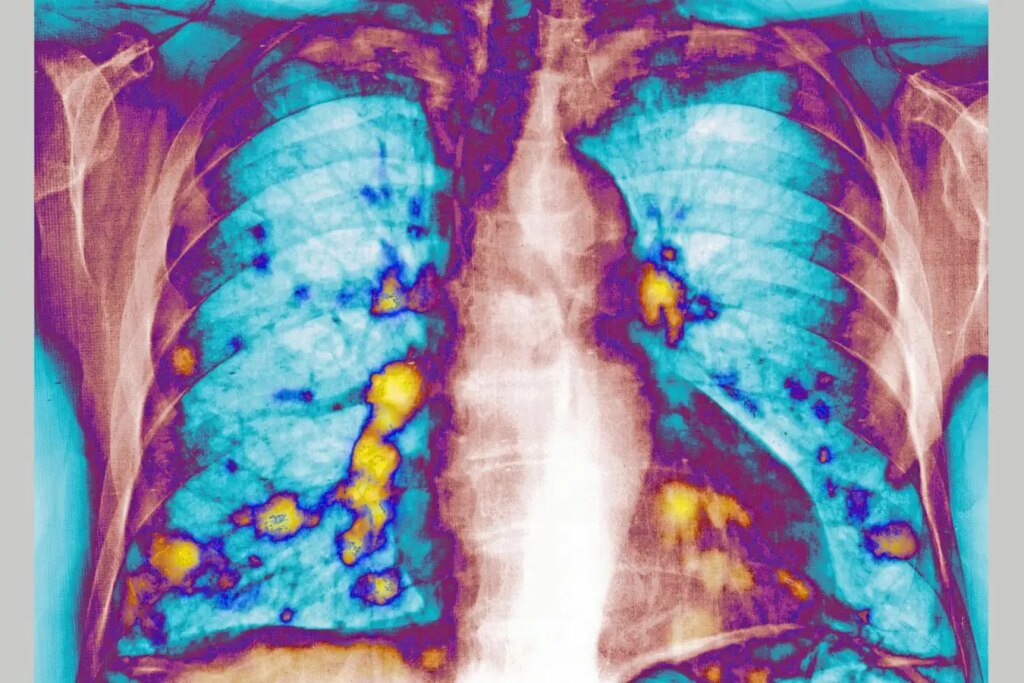

The lungs as a common site for cancer metastasis

Cavallini James/BSIP/Universal Images Group/Getty Images

The implications of respiratory infections, including influenza and COVID-19, on cancer metastasis are captivating researchers, especially given the lungs’ susceptibility as a common site for such spread.